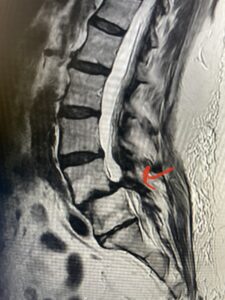

Another patient is a 62 year-old female with progressive low back pain and right leg pain and numbness that radiates to the top of her foot. She tried physical therapy and epidural injections. MRI demonstrated severe L3-4 stenosis and a grade 1 spondylolisthesis (Fig 4). There was L5-S1 and L4-5 disc collapse with modic end-plate changes. Biomechanically because of the significant degeneration of these disc spaces which stiffened the L4-S1 segment more stress was placed on the L3-4 segment, resulting in significant premature degeneration and compensatory stenosis and segmental instability. The MRI also showed pathologically, because of the slip, the L3 inferior processes were more anteriorly oriented and hence contributing to the majority of the lumbar canal compromise. Note the more sagittally-oriented facets in this case compared to the prior case (Fig 5). The patient underwent a decompressive laminectomy with attention of removing the inferior processes of L3 to fully decompress the canal. We also performed an L3-4 fusion with instrumentation (Fig 6). The patient had an uneventful postoperative course with improvement of leg pain. Of note with relief of the disabling leg pain patients are generally very happy. Patients can often manage their low back pain; it is the leg pain that they just can’t tolerate.

Fig 4: Sagittal T2-weighted lumbar MRI demonstrating L3-4 grade 1 spondylolisthesis with severe stenosis (blue arrow)